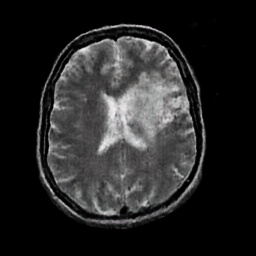

In this paper, we propose a bidirectional learning model, known as dual contrast cycleGAN (DC-cycleGAN), for medical image synthesis from unpaired data. Specifically, a dual contrast (DC) loss is formulated that leverages the advantage of samples from the source domain as negative samples to indirectly build constraints between real source and synthetic images via discriminators, and synthesize images more related to the target domain by enforcing the synthetic images to fall far away from the source domain. In addition, structural similarity index (SSIM) [35] and cross-entropy (CE) [48] are integrated into the DC-cycleGAN structure to avoid disappearing gradient information that is caused by a mean absolute error (MAE) and synthesizing irrelevant images. SSIM considers luminance [35] and CE converges fast as its back-propagation error is less than MSE [28]. As can be seen in Figs. 1 and 2, using SSIM and CE with dual contrast can generate more clear and accurate MR images as compared with that of MAE and MSE, and SSIM and CE without dual contrast loss. Although both SSIM and CE with dual contrast and without dual contrast generate similar CT images, SSIM and CE with dual contrast quantitatively generate better images as shown in Table 4. The experimental results indicate that DC-cycleGAN is able to consider more complex features such as structure in synthesizing images and produce remarkable results as compared with other state-of-the-art methods reported in the literature.

Tables 3 and 4 show the results of MR and CT synthesis, respectively. As can be seen, all components play vital role in both tables. SSIM & CE (w) performs significantly better than other losses in synthesizing MR images. This also can be seen visually in Fig. 1. In contrast, SSIM&CE (w) performs slightly better than SSIM&CE (wo) in synthesizing CT images, both generate more or less similar CT images (see Table 4).